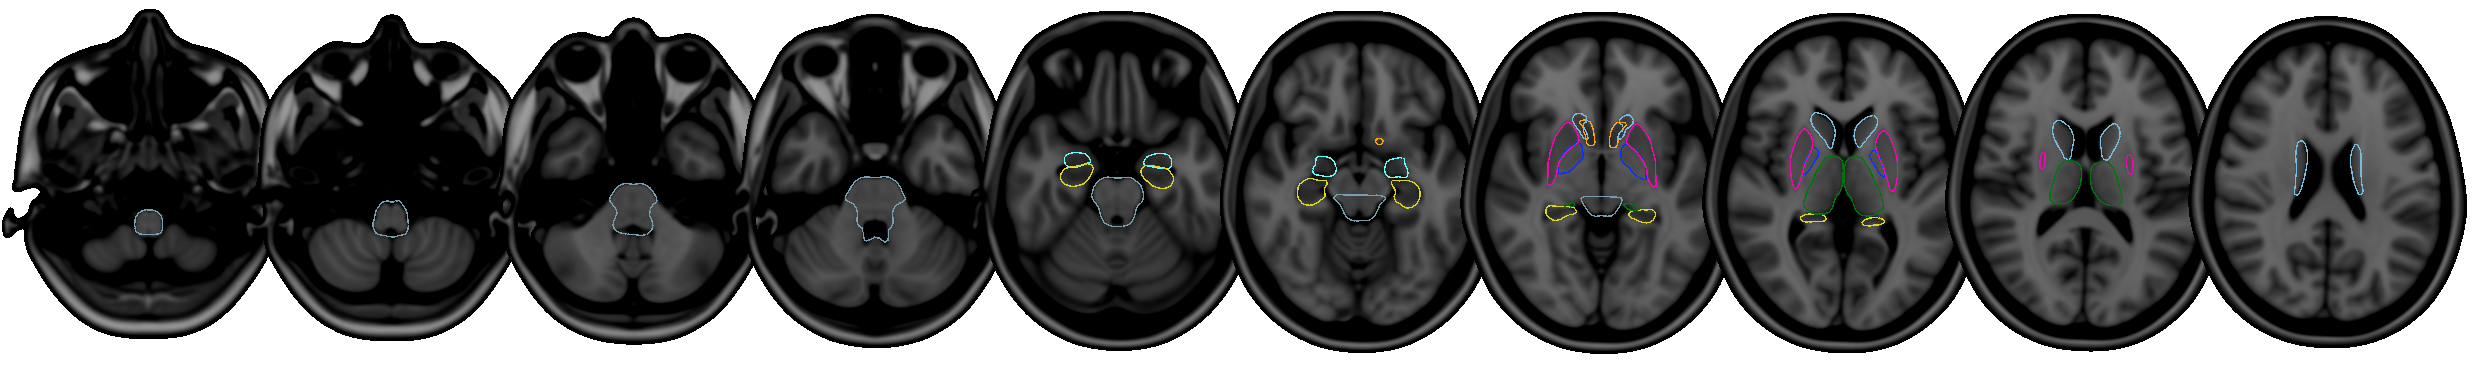

FIRST is a model-based segmentation/registration for automatic segmentation of a number of subcortical structures.

The supported structures are listed below. To segment these structures, FIRST needs a good quality T1-weighted image:

- Putamen (

Puta) - Caudate nucleus (

Caud) - Nucleus accumbens (

Accu) - Globus pallidus (

Pall) - Hippocampus (

Hipp) - Amygdala (

Amyg) - Thalamus (

Thal) - Brainstem (

BrStem)

Supported structures

The structures that FIRST can segment are listed below. The Abbrevbiated name column gives the name that you should pass to the FIRST command-line tools when you want to segment a specific structure. The Integer label column gives the integer label that FIRST assigns to each structure in its output files (e.g. output_*_firstseg.nii.gz). The Modes column gives the recommended number of modes of variation to use for each structure when fitting the subcortical model (note that this is normally taken care of automatically for you).

| Structure | Abbreviated name | Integer label | Modes |